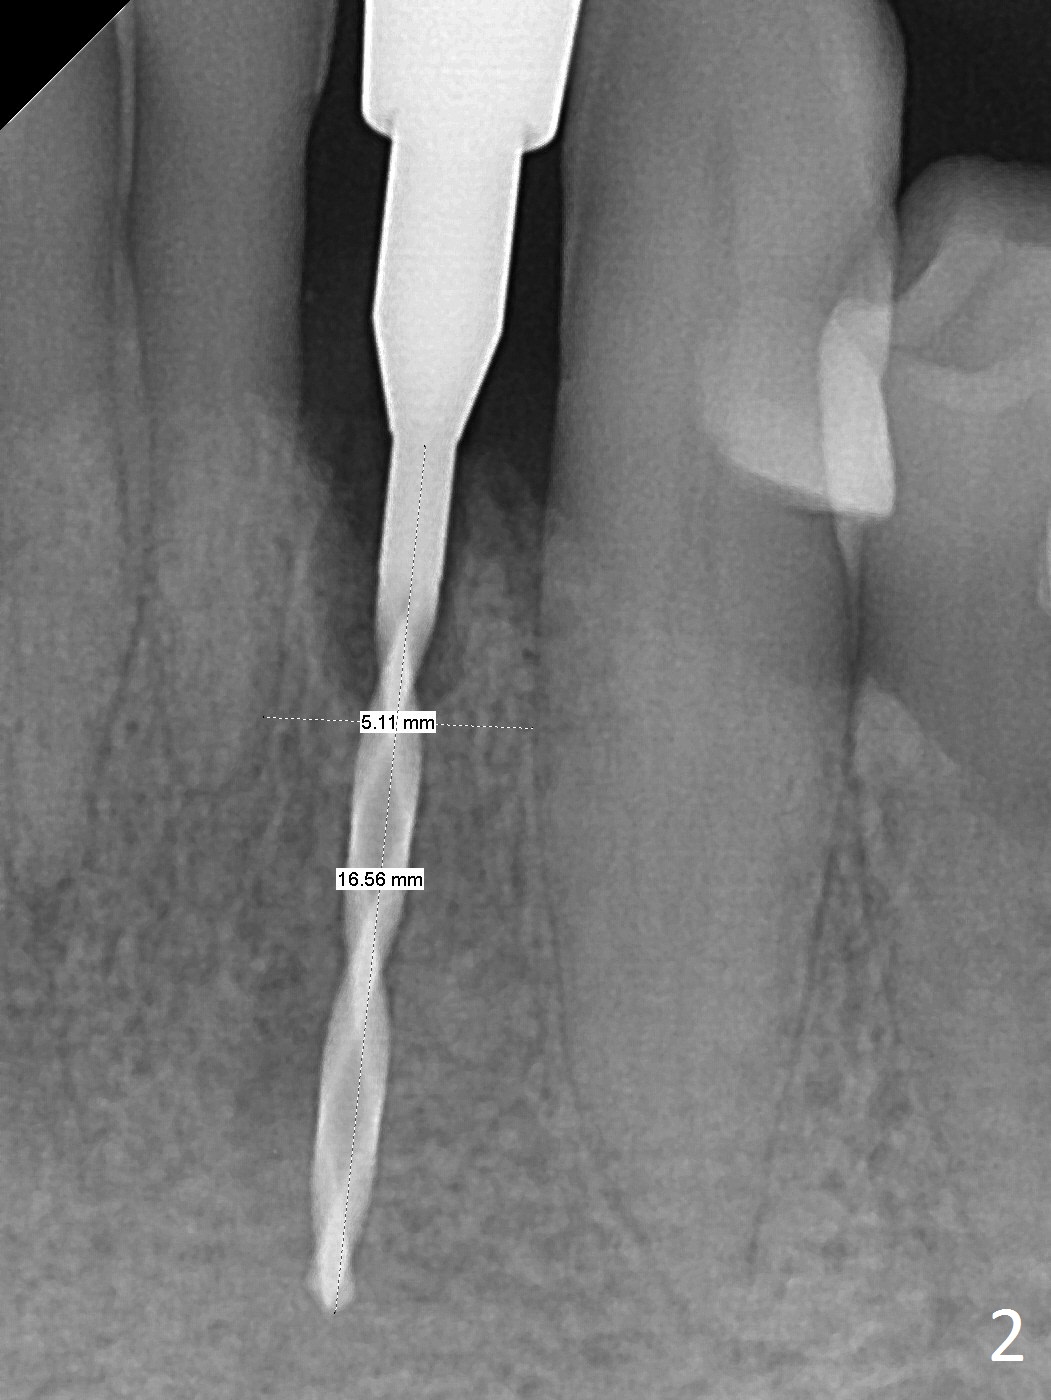

The tooth #23 is going to be extracted because the patient cannot masticate normally with mobility (Fit.1). The gingival depth is measured 2-4 mm after extraction. The 1st intraop PA taken with 1.2 mm drill for 16 mm shows the mesiodistal width is 5.11 mm (Fig.2); a 2.5x14(2) mm 1-piece implant is placed with >35 Ncm (Fig.3 with allograft placed). Following abutment preparation, an immediate provisional is fabricated to close the socket (Fig.4 P). There is no bone loss (Fig.5) or gingival inflammation (Fig.6 after reprep) 3 months postop. The narrow implant (2.5 or 2.0 mm) is indicated in the narrow edentulous space. The distal crest seems to be reduced in density and lower in height 1 year 7 months (Fig.7) and 1 year 11 months (Fig.8) post cementation. The severity does not worsen probably related to use of water pik. The crown looks bulky probably due to too large the abutment and too buccal placement of the implant (Fig.9, 10, as compared to Fig.1). A 2 mm implant may help?